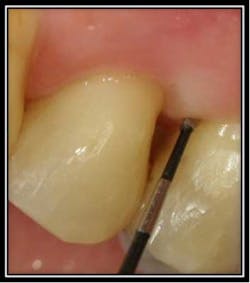

By Dr. Robert Gottlieb and Suzanne Newkirk, RDH The below pictures and corresponding video show an enamel pearl found on a molar tooth that developed a periodontal infection with a 6mm pocket depth. With Perioscopy, the doctor removed the enamel pearl quickly and efficiently with no post treatment discomfort or downtime for the patient.

Post enameloplasty the root is clean

3 months post treatment pocket is now 3mm